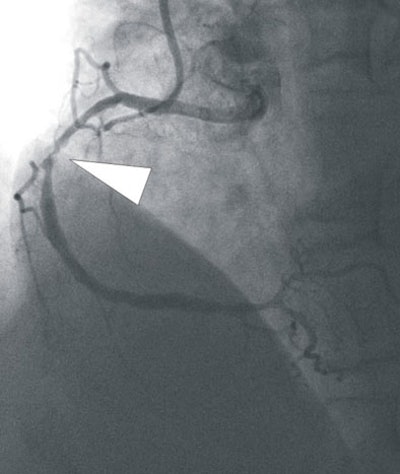

![]() |

| In a 64-year-old man with chest pain, conventional catheter angiography confirmed the coronary CTA findings, and described a 50% ostial stenosis with diffuse disease throughout the vessel and a discrete 90% stenosis in the mid right circumflex artery (RCA) (arrows). |

"Segmental comparison was performed between coronary CTA and (DSCT) myocardial segments," they wrote. "Results were also compared with findings at SPECT and/or invasive catheter angiography. Data were analyzed using the Bayesian model."